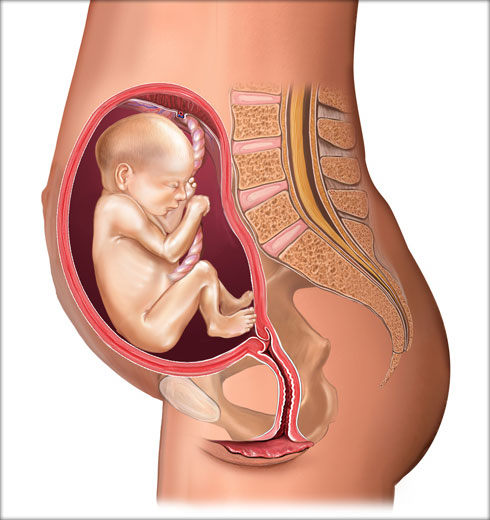

од зачећа 38 недеља